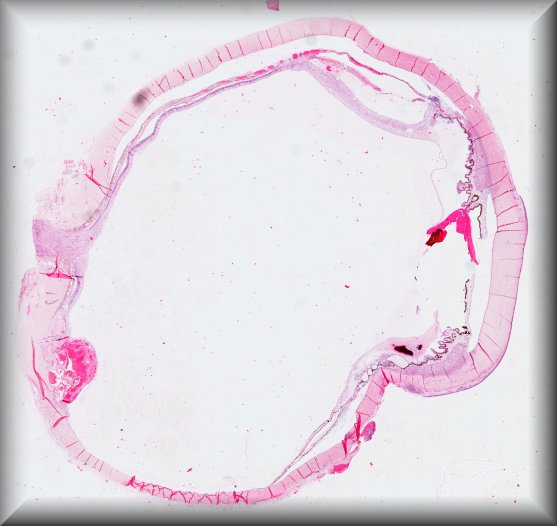

Steffen Heegaard (Copenhagen): Haemolacria in a 72-year-old man. Protocol |